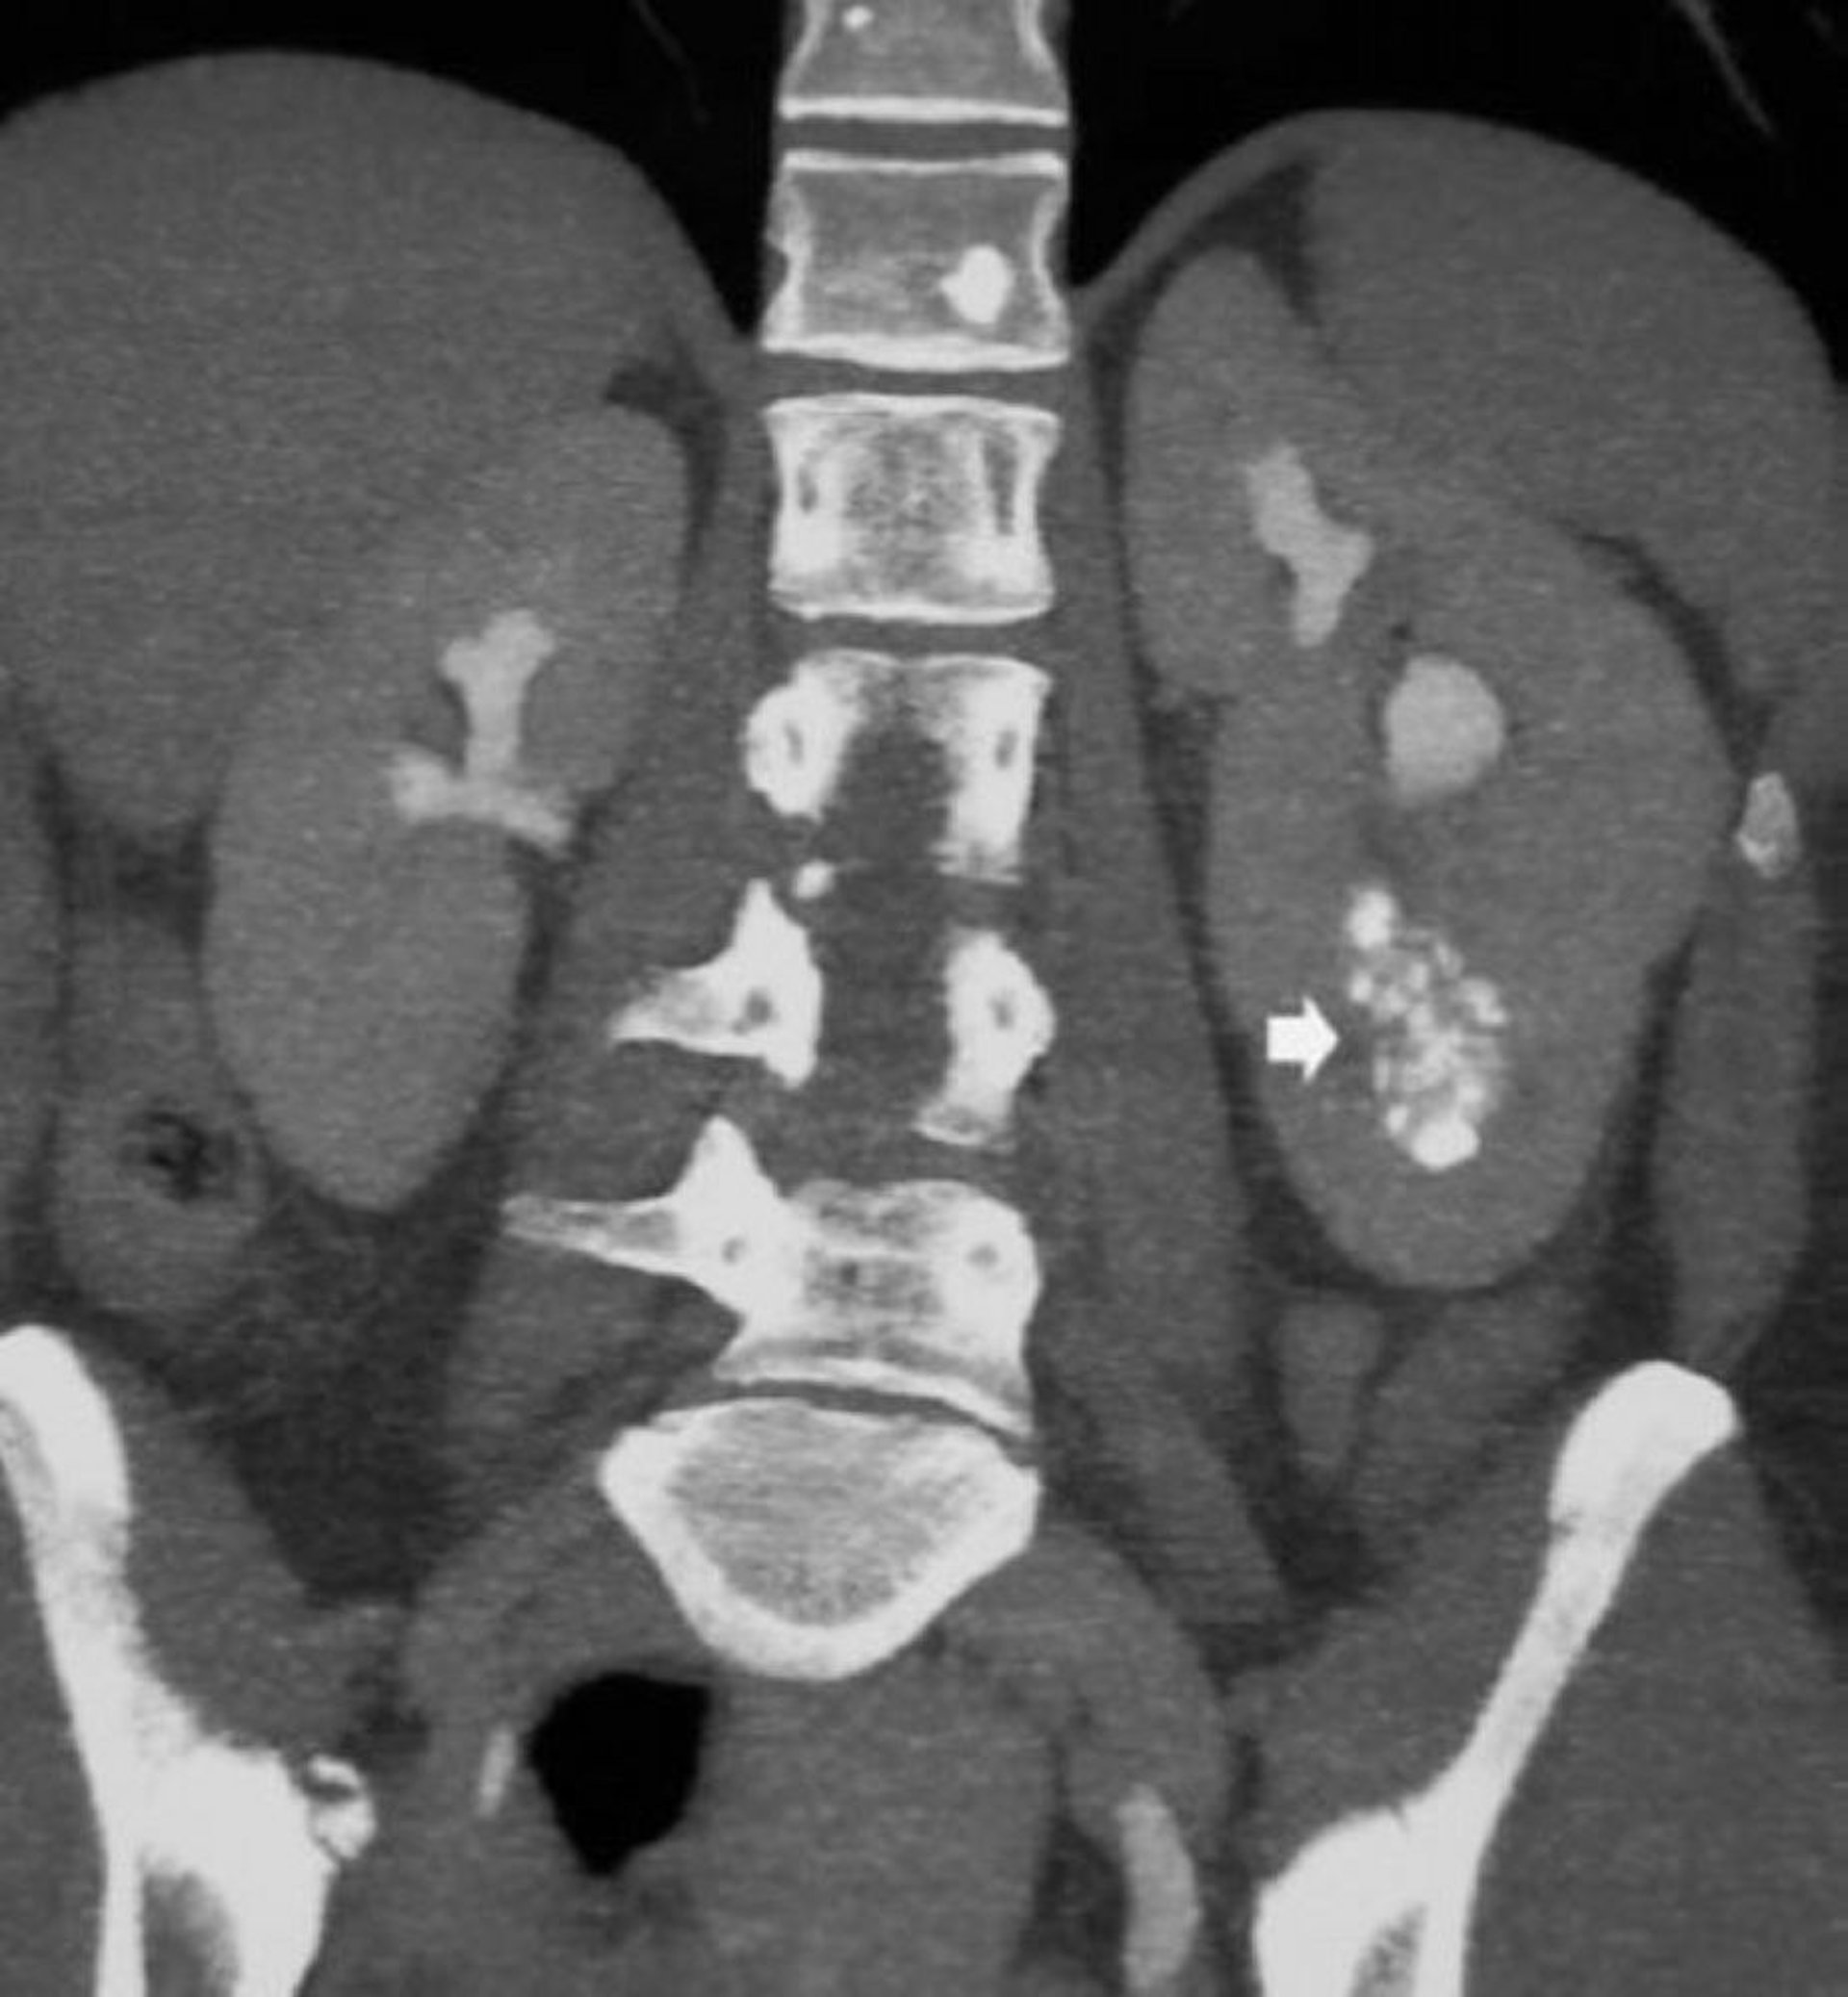

La diagnosi viene sospettata in pazienti con calcoli o infezioni delle vie urinarie ricorrenti o sulla base di riscontri RX incidentali come nefrocalcinosi midollare e dotti dilatati pieni di contrasto. Tipicamente, l'analisi delle urine mette in evidenza un'acidosi tubulare renale distale incompleta (una franca acidosi metabolica è rara) e una ridotta capacità di concentrazione urinaria in pazienti che non presentano poliuria sintomatica.

La diagnosi viene generalmente confermata mediante la TC, ma si può fare ricorso anche all'urografia EV. L'ecografia non è utile perché le cisti sono piccole e localizzate profondamente nella midollare.